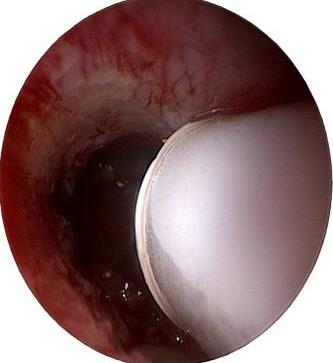

摘要:目的 分析医用生物蛋白胶应用于耳内镜下鼓膜修补术的临床疗效。方法 回顾性分析2022年10月-2023年10月该院收治的60例单纯鼓膜穿孔患者的临床资料,根据手术方法不同,将患者分为研究组和对照组,各30例。研究组术中使用医用生物蛋白胶粘合残余鼓膜和修补材料;对照组术中采用明胶海绵覆盖修补鼓膜。观察两组患者术后的鼓膜愈合情况(鼓膜愈合率、愈合时间、干耳时间和外耳道上下径)和并发症发生情况;于手术前后,采用纯音测听法(500、1 000、2 000、4 000 Hz),测量两组患者气导阈值,观察听力改善程度;采用视觉模拟评分法(VAS)评分,评估患者术后疼痛程度。结果 两组患者术后鼓膜愈合率、愈合时间、外耳道上下径和并发症发生率比较,差异均无统计学意义(P > 0.05)。研究组术后平均气导听阈明显低于对照组,差异有统计学意义(P < 0.05)。研究组术后干耳时间短于对照组,术后第1天疼痛VAS评分明显低于对照组,差异均有统计学意义(P < 0.05)。结论 医用生物蛋白胶应用于耳内镜下鼓膜修补术,可有效地降低气导听阈,缩短干耳时间,减轻患者疼痛,且不增加并发症发生率,值得临床推广应用。